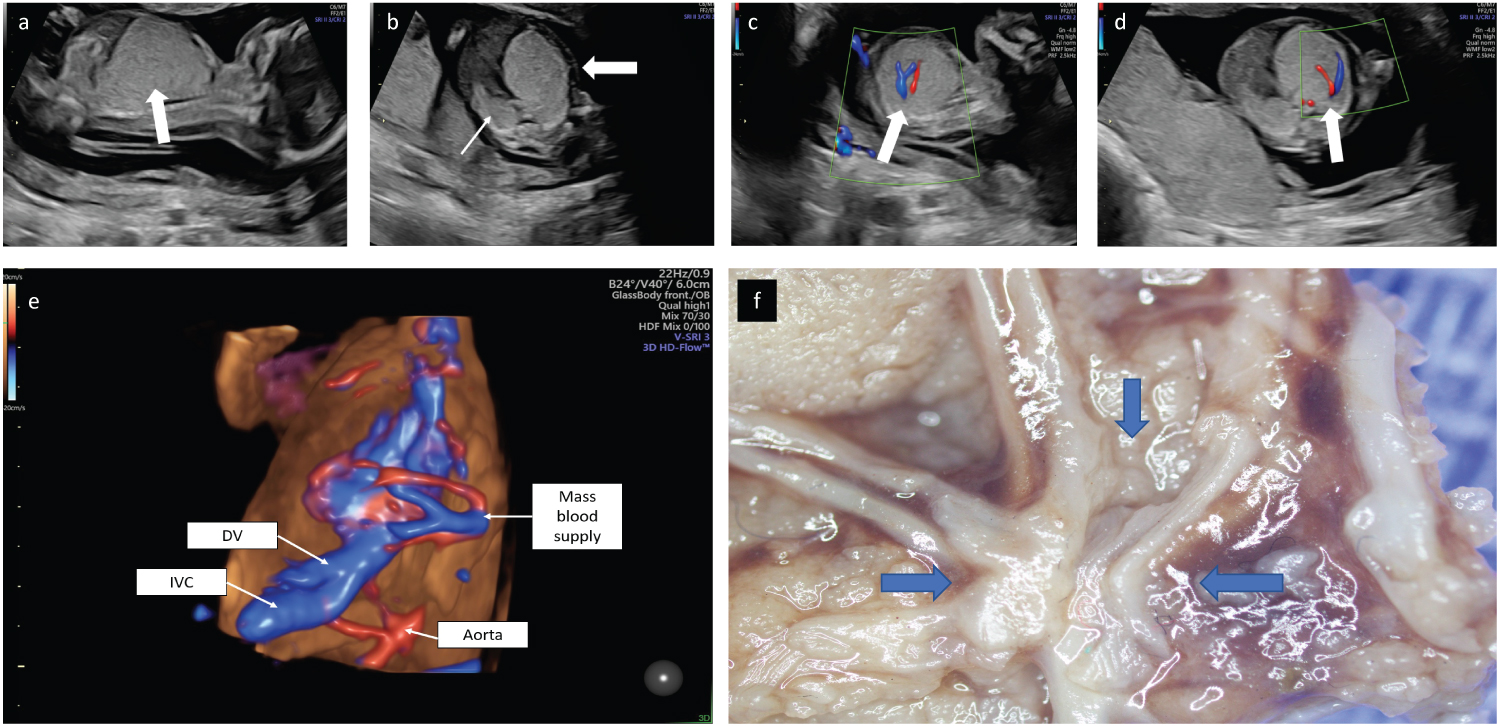

A 30-year-old patient, gravida 2 para 1 presented at 15 weeks of gestation. The parents were generally healthy with no remarkable family history. Nuchal translucency scan was normal. Sonographic examination revealed an appropriate for gestational age male fetus. Mild pericardial effusion and ascites were evident and an inverted A wave was demonstrated in the ductus venosus consistent with fetal cardiac insufficiency. The left apical heart was shifted to the right and the stomach was in a central position (mesogastria). The left lung was comprised of an echogenic mass with a measured circumference in an axial plane of 91 mm. No macro-cystic lesions were evident (Figure 1a, Figure 1b). Two large vessels exhibiting systemic venous and arterial flow were demonstrated entering the mass to form a vascular plexus (Figure 1c, Figure 1d, Figure 1e, Figure 1f). The diaphragm was flattened by the enlarged left lung. The right lung was compressed backwards and small (measured circumference in an axial plane 48 mm). A detailed anatomical scan did not reveal any further malformations. Following a comprehensive consultation regarding the findings, the parents elected termination of pregnancy.

Figure 1: a) 2D ultrasound obtained at 15.4 weeks of gestation. Mid-sagittal plane demonstrating an echogenic mass that comprised the left lung with a caudal mass effect, compression of the diaphragm and abdominal organs. b) Axial view demonstrating the mass effect leading to a right shift of the heart (bold arrow). The right lung is small and compressed posteriorly (thin arrow). c) 2D Doppler flow in a parasagittal view demonstrating a large artery and a large vein at the center of the mass (arrow). d) 2D Doppler flow axial view demonstrating a large artery and vein at the center of the mass (arrow). e) 3D Doppler flow of the vessels within the thoracic mass. f) Stereotactic dissection demonstrated a plexus of aberrant vessels within the mass. View Figure 1